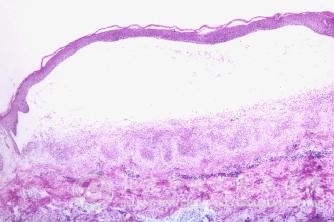

紫外线性皮炎的症状有什么?北京京城皮肤医院指出,紫外线性皮炎是常见的皮肤病类型中的一种,常常由于各种原因引起紫外线性皮炎,紫外线性皮炎皮肤症状表现复杂,而且紫外线性皮炎发展迅速。北京京城皮肤医院就给大家讲解紫外线性皮炎的症状有什么。帮助大家及早的发现紫外线性皮炎,预防紫外线性皮炎的发生。

北京京城皮肤医院指出,紫外线性皮炎的症状:主要分布在颜面、颈部和手背等曝光部位,尤以额部、面颊为多。一般患处皮肤色素增加,可持续多年复发。